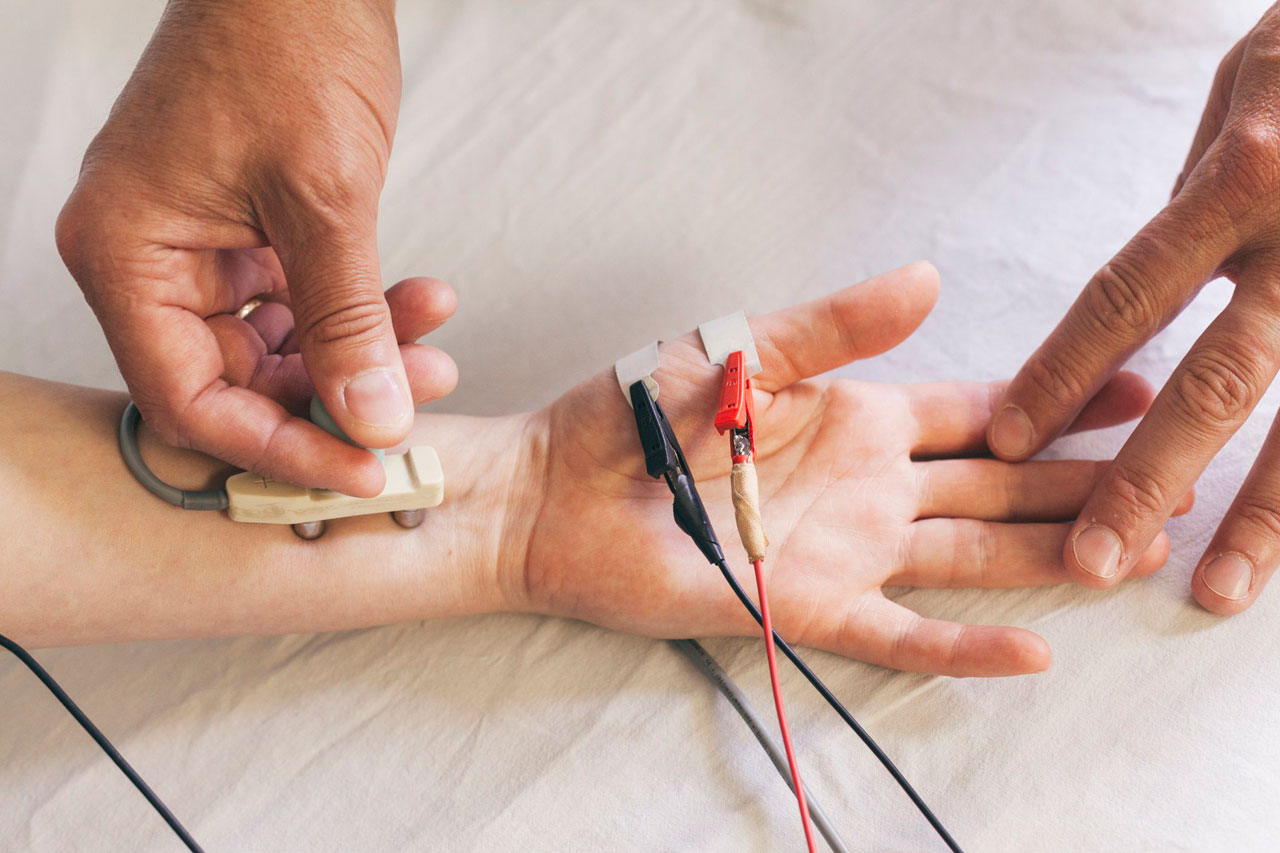

Avalia a função dos nervos e músculos para identificar alterações neuromusculares.